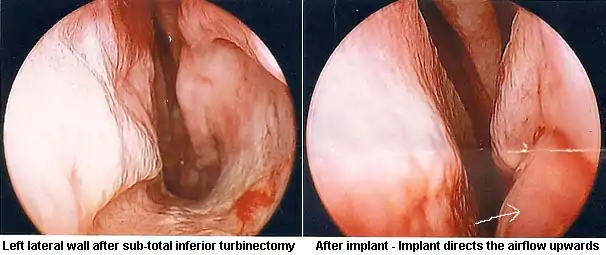

In some people, surgery to restore missing or reduced turbinates or various fillers that correct the airflow in the nose may be beneficial.[3] Corrective surgical methods are experimental and limited to a few ENT practitioners worldwide.

A 2015 meta-analysis identified 128 people treated with surgery from eight studies that were useful to pool, with an age range of 18 to 64, most of whom had been experiencing ENS symptoms for many years. The most common surgical approach was creating a pocket under the mucosa and implanting material - the amount and location were based on the judgement of the surgeon. In about half the cases a filler such as noncellular dermis, a medical-grade porous high-density polyethylene, or silastic was used and in about 40% cartilage taken from the person or from a cow was used. In a few cases hyaluronic acid was injected and in a few others tricalcium phosphate was used. There were no complications caused by the surgery, although one person was over-corrected and developed chronic rhinosinusitis and two people were under-corrected. The hyaluronic acid was completely resorbed in the three people who received it at the one year follow up, and in six people some of the implant came out, but this did not affect the result as enough remained. About 21% of the people had no or marginal improvement but the rest reported significant relief of their symptoms. Since none of the studies used placebo or blinding there may be a strong placebo effect or bias in reporting.[9]